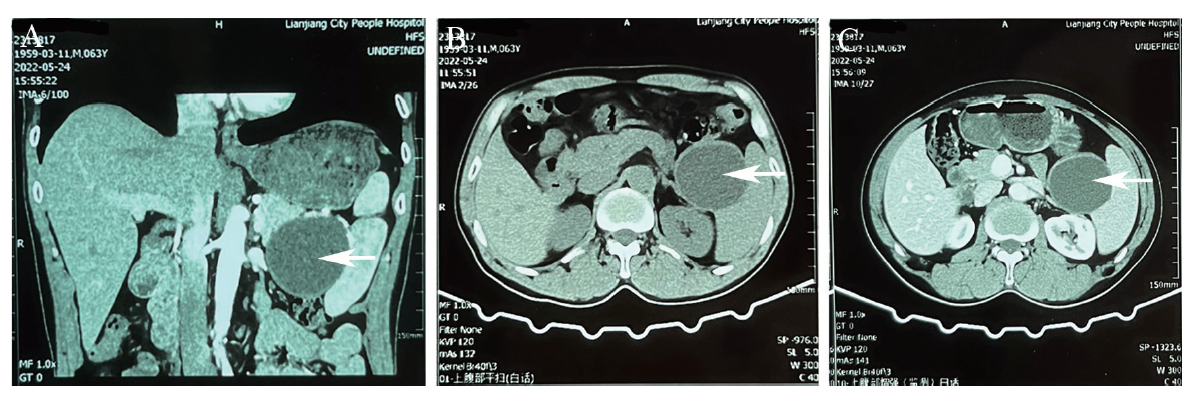

患者入院初步诊断为胰腺肿物性质待查,2022年5月26日于我院行超声内镜(EUS),镜下可见胃底静脉显露,胃体黏膜光滑,胃窦黏膜充血水肿,球部及降段黏膜光滑,十二指肠乳头黏膜未见异常。超声下见胰头、颈体形态规则,内部回声均匀;胰体尾区域见一切面大小69.4 mm×58.4 mm均匀无回声占位,内未见分隔,囊壁稍厚,见一切面大小13.5 mm×9.4 mm稍高回声结节影,与囊壁分界不清,病灶远场强化;主胰管不宽,与占位病变不相通;胆总管未见扩张;彩色多普勒超声显示病灶内未见血流信号;弹性成像显示质软,弹性应变率= 0.72;病灶压迫脾静脉,胃底区域管壁内、外均见不规则血流信号(图2A~C)。拟行细针穿刺活检(FNA),用ECH0-19型超声内镜穿刺针在超声内镜引导下于胃体插入无回声病灶内,抽取出棕褐色液体共110 mL,拉丝实验阴性,分别送常规、血液生化、肿瘤标志物及脱落细胞学检查(图2D)。考虑胰体尾囊性占位:囊腺瘤?假性囊肿?囊液常规:腺苷脱氨酶119.4 U/L(参考值0~20 U/L)。囊液生化:李凡他试验阳性。囊液癌胚抗原767.10 ng/mL(参考值0~15 ng/mL)。囊液穿刺细胞学:见红细胞及少许组织细胞和淋巴细胞,考虑胰腺良性病变。

图2 一例PLEC患者彩色多普勒超声内镜图及抽取的囊液

注:A为胰体尾区域见均匀无回声占位,内未见分隔,囊壁稍厚,见一切面稍高回声结节影,与囊壁分界不清;B为病灶远场强化;C为主胰管不宽,与占位病变不相通,胆总管未见扩张;D为抽取的囊液。